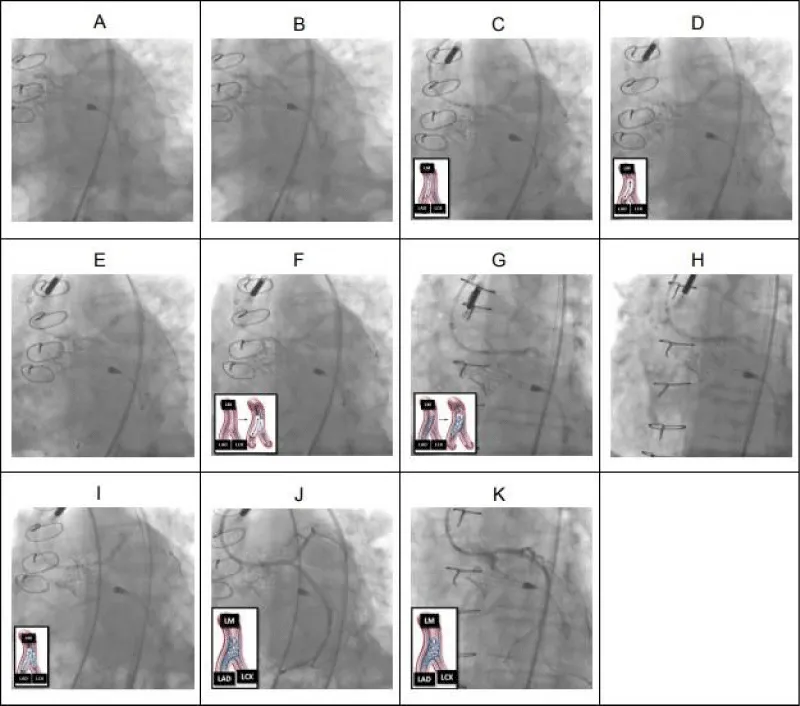

Details of this intervention are described here (Figure 2).

Figure 2: LM DK-Crush bifurcation PCI. (A) Pre-dilation (2.5 x 12 mm balloon) of ostial LAD. (B) Pre-dilation (2.5 x 12 mm balloon) of ostial LCX. (C) 3.0 x 12 mm drug-eluting stent (DES) deployed across LCX lesion with proximal portion of DES in the distal LM. (D) LCX wire removed and DES in LCX “crushed” with a 3.0 x 12 mm NC balloon extending from the LM to the LAD. (E) LCX rewired through “crushed” LCX stent and the struts of the “crushed” LCX stent were dilated with a 2.5 x 12 mm non-compliant balloon. (F) The first simultaneous kissing balloon inflation (SKBI) of the DK-Crush bifurcation PCI technique was performed using 3.0 x 12 mm and 2.5 x 12 mm non-compliant balloons in the LAD and LCX, respectively. The 3.0 x 12 mm non-compliant balloon was also used to pre-dilated the ostial LM (not shown). (G) Using IVUS-guidance, a 3.0 x 23 mm DES was positioned in multiple orthogonal views to span both the ostial LM and ostial LAD lesions before being deployed. The first proximal optimization technique (POT) was performed (not shown). (H) The proximal portion of the LM-LAD stent was flared with a 3.5 x 12 mm non-compliant balloon at high pressures. (I) After rewiring the LCX through the LM-LAD stent, 3.5 x 12 mm non-compliant balloons were positioned across both the LM-LAD and LM-LCX and the second SKBI was performed. A second POT was subsequently performed using the 3.5 x 12 mm non-compliant balloon (not shown). (J) Final result of the LM bifurcation (IVUS not shown but demonstrated excellent stent expansion and apposition without any evidence of edge dissection). (K) Final result of the ostial LM (IVUS not shown but demonstrated excellent stent expansion and apposition). (K) Final result of the ostial LM (IVUS not shown but demonstrated excellent stent expansion and apposition).